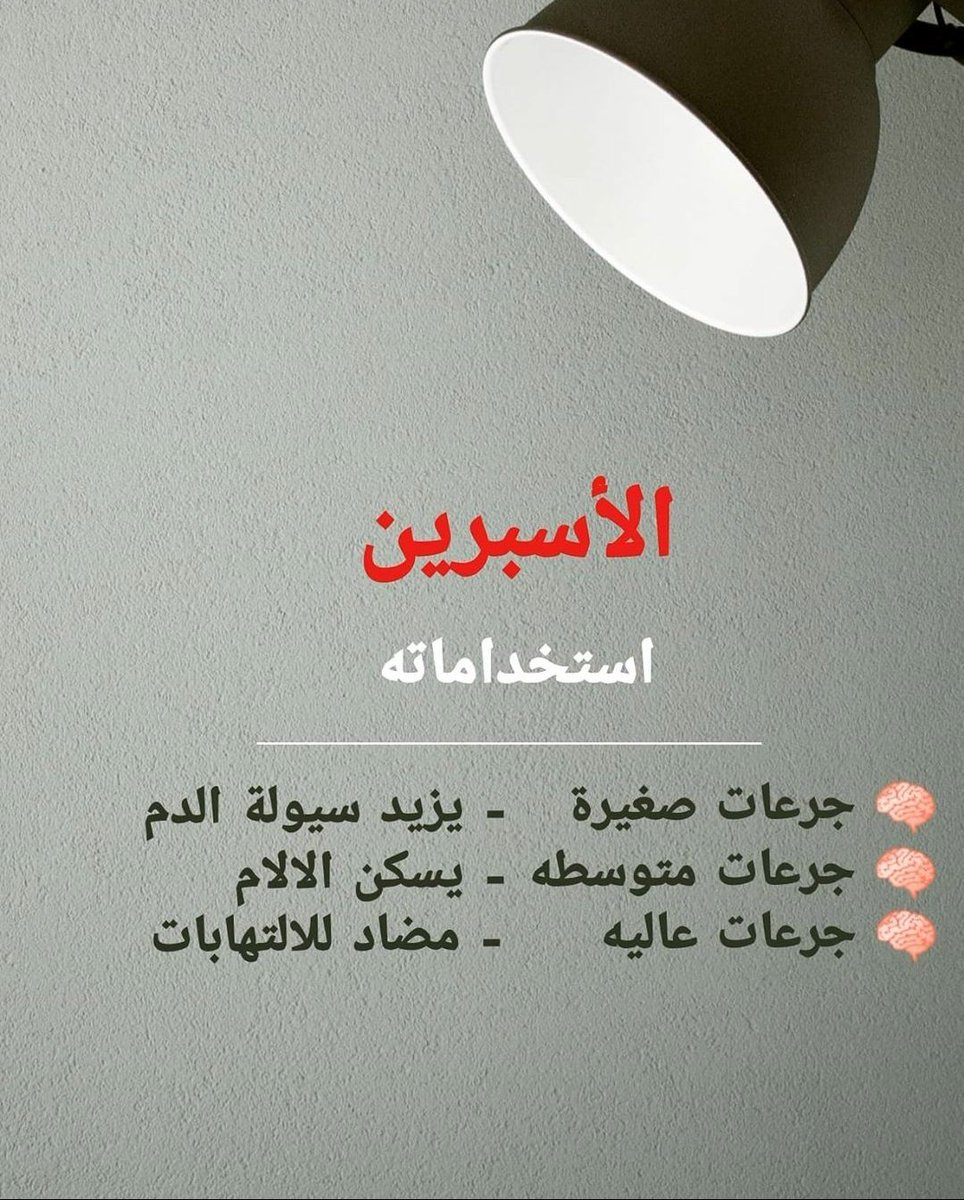

معلومات توعويه مفيدة عن #الاسبرين و #السكته_الدماغيه

☝️

💥بشكل عام

🧠لايستخدم الابتوجيه الطبيب

🧠لم تؤيد الدراسات استخدامه لمن لم يصاب بجلطه سابقه

🧠الاصل علاج سيوله صحيح واحد يكفي إلا حالات نادرة قد نحتاج اكثر

يتبع 👇👇

☝️

💥بشكل عام

🧠لايستخدم الابتوجيه الطبيب

🧠لم تؤيد الدراسات استخدامه لمن لم يصاب بجلطه سابقه

🧠الاصل علاج سيوله صحيح واحد يكفي إلا حالات نادرة قد نحتاج اكثر

يتبع 👇👇

معلومات توعويه مفيدة عن #الاسبرين و #السكته_الدماغيه_الاقفاريه✌

💥بشكل عام

🧠الاصل علاج سيوله صحيح واحد يكفي إلا حالات نادرة قد نحتاج اكثر

♦️فلو استخدمت الاسبرين+البلافكس أو ادويه سيوله اخرى كالوارفارين تأكد من طبيبك المدة والسبب

💥بشكل عام

🧠الاصل علاج سيوله صحيح واحد يكفي إلا حالات نادرة قد نحتاج اكثر

♦️فلو استخدمت الاسبرين+البلافكس أو ادويه سيوله اخرى كالوارفارين تأكد من طبيبك المدة والسبب